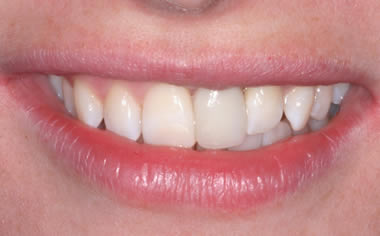

Missing upper front tooth replaced by dental implant and crown